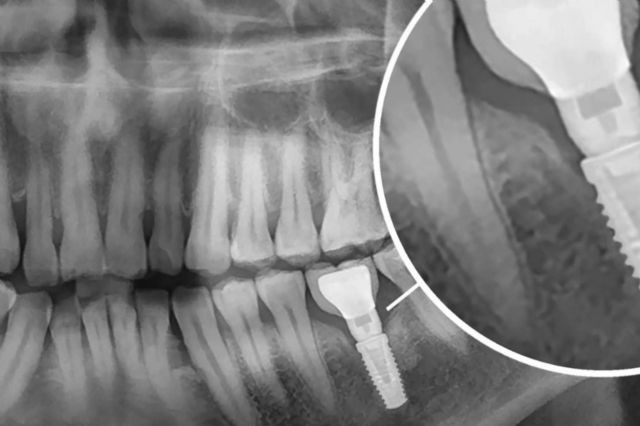

Al elegir los implantes dentales como método para reponer la pérdida de dientes, las personas reciben una solución fija, cómoda, funcional, resistente, duradera y estética que se adapta con precisión a su zona bucodental. Lo anterior se debe a que los implantes se ubican en los huesos maxilares, justo bajo las encías para garantizar su agarre, ya que se fusionan con el hueso alveolar.

La propuesta de la Clínica Dental Dr. Román Hernández resalta por dar inicio con una revisión dental completa de la boca que detalla el estado de cada paciente para proceder al procedimiento más idóneo. Seguidamente, se lleva a cabo un estudio radiológico que muestra los tejidos óseos en cuanto a cantidad y calidad del hueso. Cuando dichos estudios finalizan, se procede a determinar el tipo de implante ideal, sea implante unitario, puentes dentales, prótesis dentales o injerto de hueso.